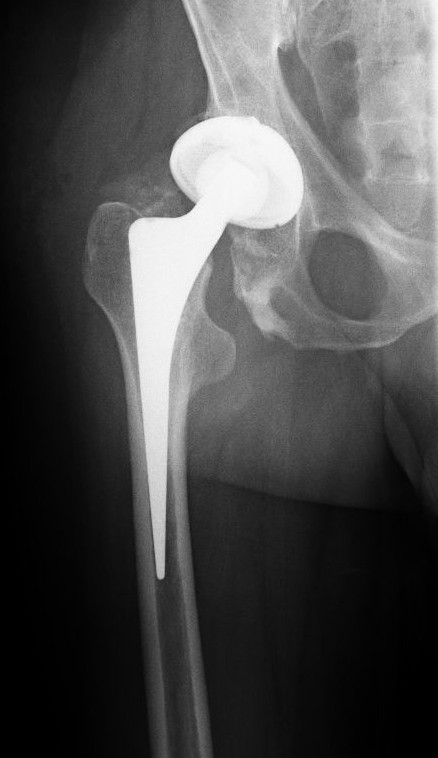

Röntgenbild einer konventionellen, zementfrei eingesetzten Endoprothese des Hüftgelenkes (Abkürzung: HTP oder H-TEP). Das große Metallimplantat erscheint auf der Aufnahme fast weiß, stellenweise durchscheinend. Die künstliche Pfanne ist aus relativ dünnem Material und mit einem Polyethylen-Lager ausgekleidet. Schemenhaft zeigt sich in der großen Auflösung die Metallkugel, die den Hüftkopf ersetzt.

Foto: User:Scuba-limp

Lizenz: GFDL